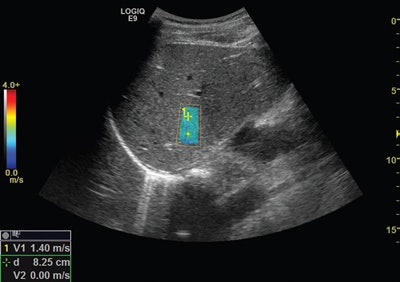

The firm is introducing the Logiq XDclear family, which provides a wider portfolio of probes, sophisticated anatomical models and a package of features aiming to improve clinical confidence with difficult-to-scan patients. The system offers a range of dedicated autooptimization and assistance tools to improve both productivity and the patient experience, through solutions intended to reduce the need for invasive tests and resulting patient discomfort.

This latest offering includes Logiq E9 XDclear 2.0, a new processing chain that optimizes the imaging process from the pulse of the probe to each of its pixels, delivering excellent image quality across a wide variety of cases, according to GE. The availability of extra tools such as 3D GPS Markers, MRI Auto-Registration and specialty probes will enhance its value, the company says.